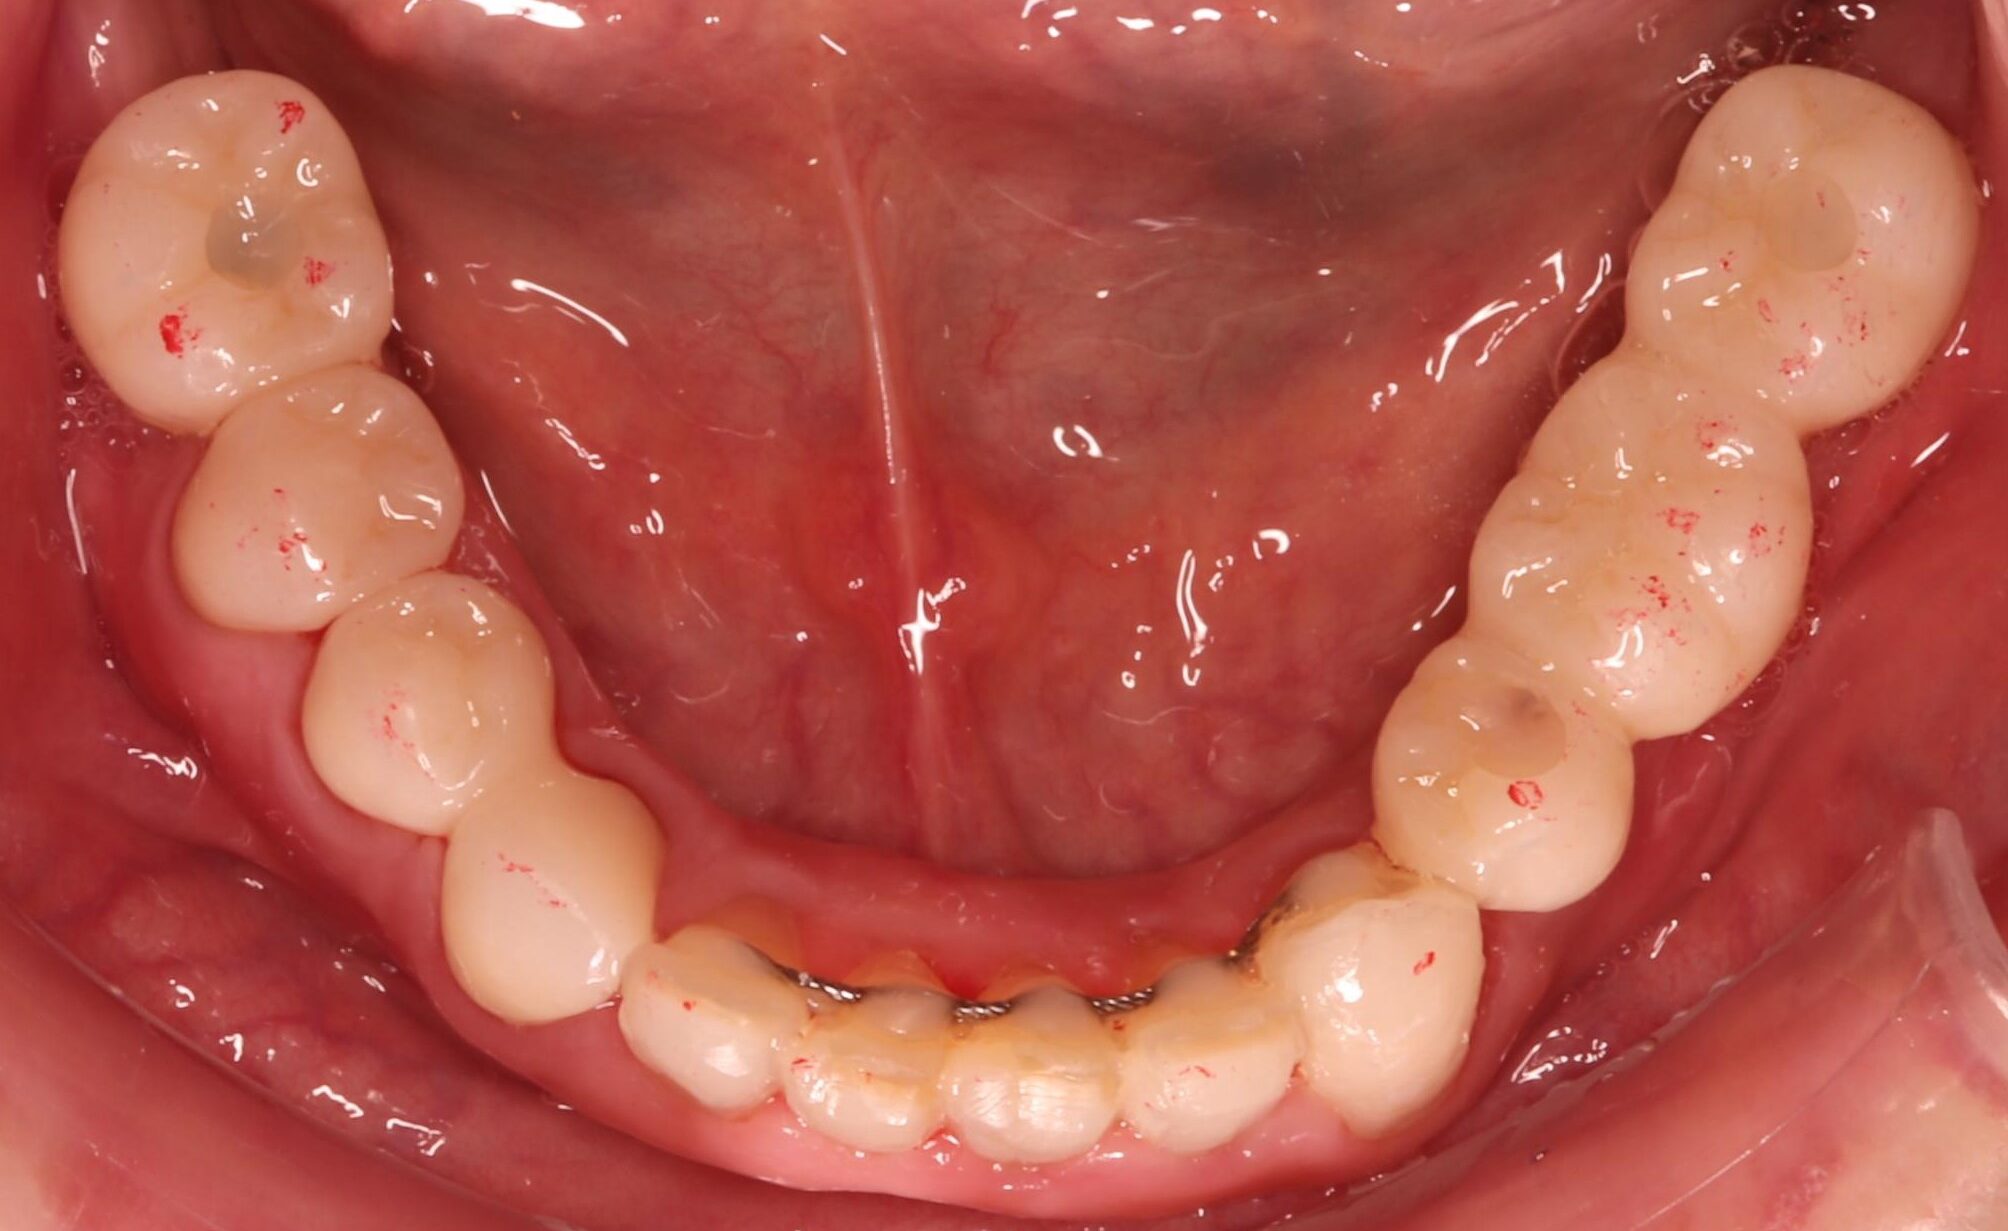

症例11

50代 男性 なんでも食べられるようになりたい

術前咬合面

術前咬合面

術後咬合面

術後咬合面

| 主訴 | 自分が一番元気に、何でも食べられる父親でいたい。家族との食事の時間が人生ですごく大切で、何とかしたい、と思っていた。 |

|---|---|

| 年代・性別 | 50代 男性 |

| 治療部位 | 上顎6~6 |

| 治療費用 |

インプラント手術料 |

| 手術回数 | 1回 |

| 治療期間 | 4ヶ月 |

| 手術時間 | 180分 |

| 治療回数 | 10回 |